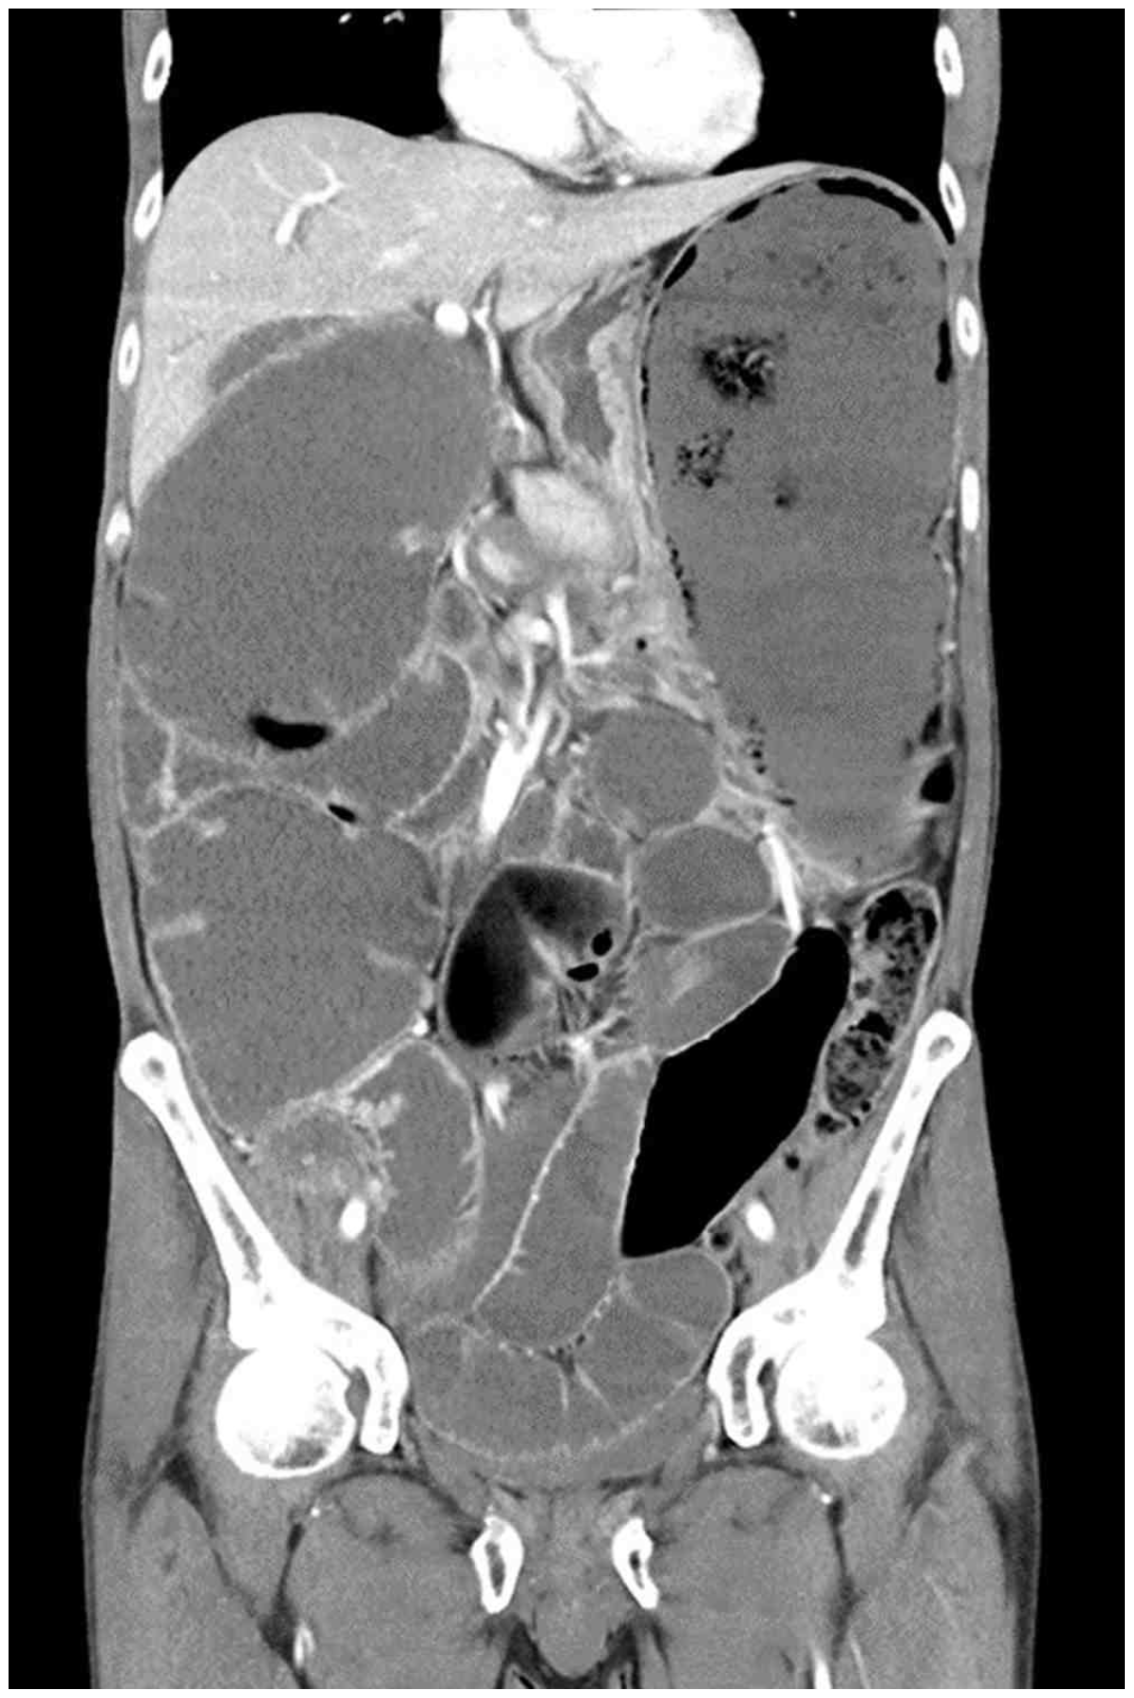

CT: Colon distension, cut-off sign

• 원인 확인을 위해 시행한 복부 CT상 colon distension이 관찰되며, sigmoid colon 근처에서 cut-off sign(대장이 확장된 부위와 정상적인 부위 사이의 경계)이 관찰되므로 장폐쇄가 의심된다.

• 항문근실조증: 항문괄약근과 골반저근육 사이의 coordination이 제대로 이루어지지 않는 골반저기능장애 질환 중 하나이다. 항문근실조증 또한 만성적인 변비를 유발할 수 있으나, 항문근실조증에 의해 증상이 발생했다면 CT상 직장/항문에 대변정체 소견이 있었을 것이다. 현재 복부 CT상 sigmoid colon 윗 부분에서 cut-off sign이 관찰되므로 항문근실조증의 가능성은 낮다고 생각된다.